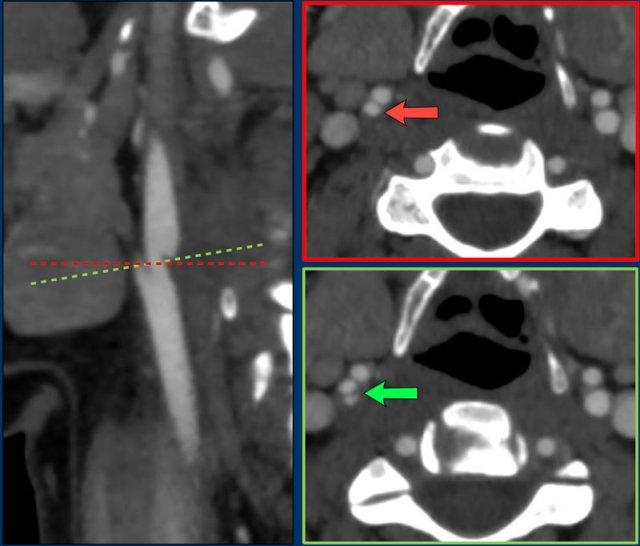

Trên mặt phẳng cắt đứng dọc của CTA, có thể thấy hình ảnh nhô ra dạng vách ngăn ở thành lưng của bầu động mạch cảnh trong (ICA).

Đây là vị trí và cấu hình điển hình của màng nhện động mạch cảnh.

Tuy nhiên, để chẩn đoán xác định màng nhện động mạch cảnh, cần phải quan sát thấy một gờ nối thành bên và thành trong của động mạch cảnh trong trên mặt phẳng cắt ngang (mũi tên ảnh bên phải).

Màng nhện động mạch cảnh có thể có kích thước khác nhau.

Trong trường hợp này, màng nhện động mạch cảnh nhỏ hơn nhiều so với ví dụ trước.

Tuy nhiên, các tiêu chuẩn chẩn đoán hình ảnh cho màng nhện động mạch cảnh vẫn được áp dụng.

Trên ảnh cắt đứng dọc, có thể thấy hình ảnh nhô ra dạng vách ngăn ở mặt lưng của động mạch cảnh trong (mũi tên ảnh bên trái).

Trên ảnh cắt ngang, có thể thấy gờ của màng nhện động mạch cảnh nối thành bên và thành trong của động mạch cảnh trong (mũi tên).

Nếu chỉ quan sát trên ảnh cắt ngang, bạn có thể bỏ sót màng nhện.

Mũi tên đỏ chỉ vào động mạch cảnh trong (ICA) và động mạch cảnh ngoài (ECA), nhưng không thấy màng nhện.

Chỉ khi nghiêng mặt phẳng cắt ngang vuông góc với trục dọc của ICA (đường xanh lá và mũi tên xanh lá), bạn mới nhận thấy màng nhện (gờ nối thành bên và thành trong của ICA).

Tất nhiên, các tái tạo ảnh đứng dọc vẫn là phương pháp tốt hơn để phát hiện màng nhện.